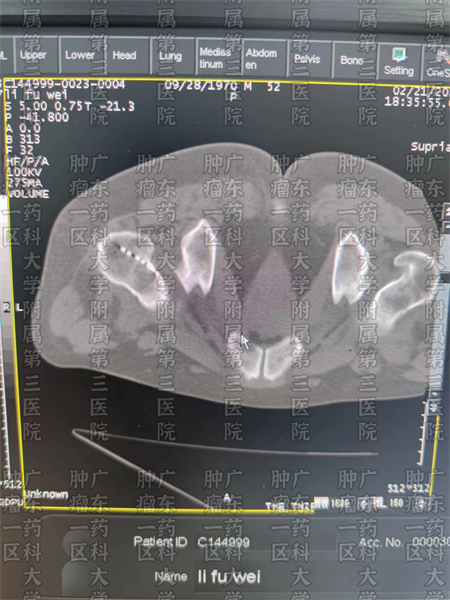

粒子植入治疗是将微小粒子植入肿瘤病灶的一种微创治疗方式,针对骨转移的患者,在经过专业的计算后,刘跃军主任会将粒子种入转移病灶中。粒子植入后,会源源不断地发出微量射线,这些射线在消灭癌细胞,缩小肿瘤病灶的同时,也会起到镇痛止痛的作用。所以,对肺癌骨转移的患者,粒子植入不仅是一种抗肿瘤治疗技术,也是一种止痛治疗方案。